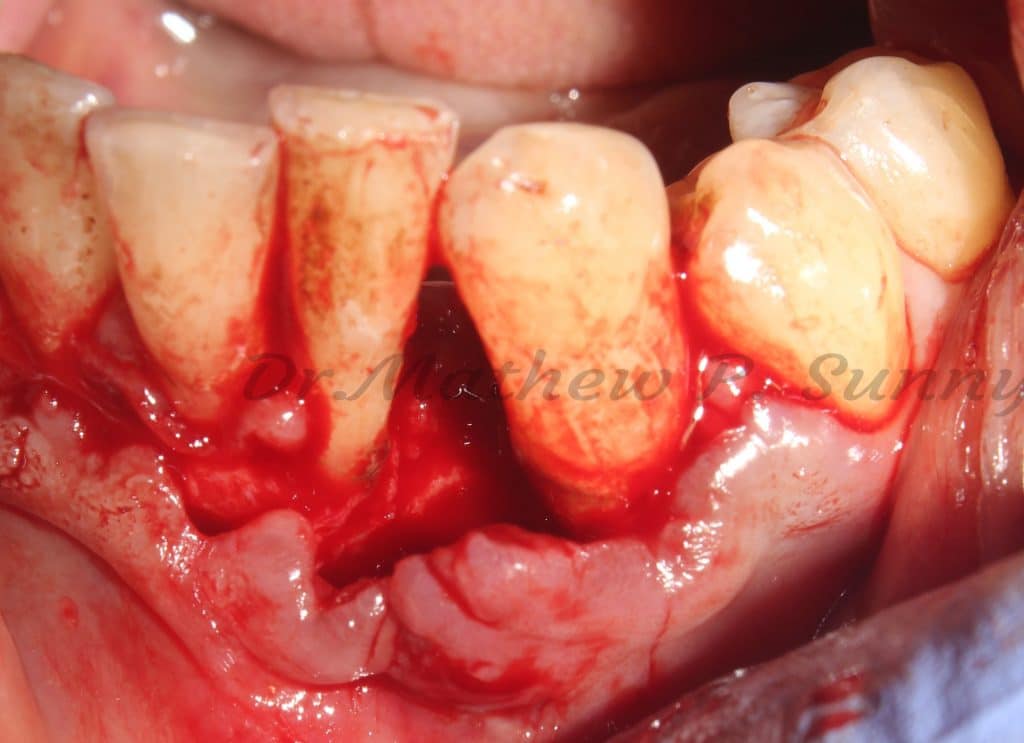

Scaling was followed by flap elevation, removal of granulation tissue and most importantly.. all subgingival calculus.

flap raised..

bone defect noted.. and all granulation tissue curreted..

subgingival calculus is noted and then removed..